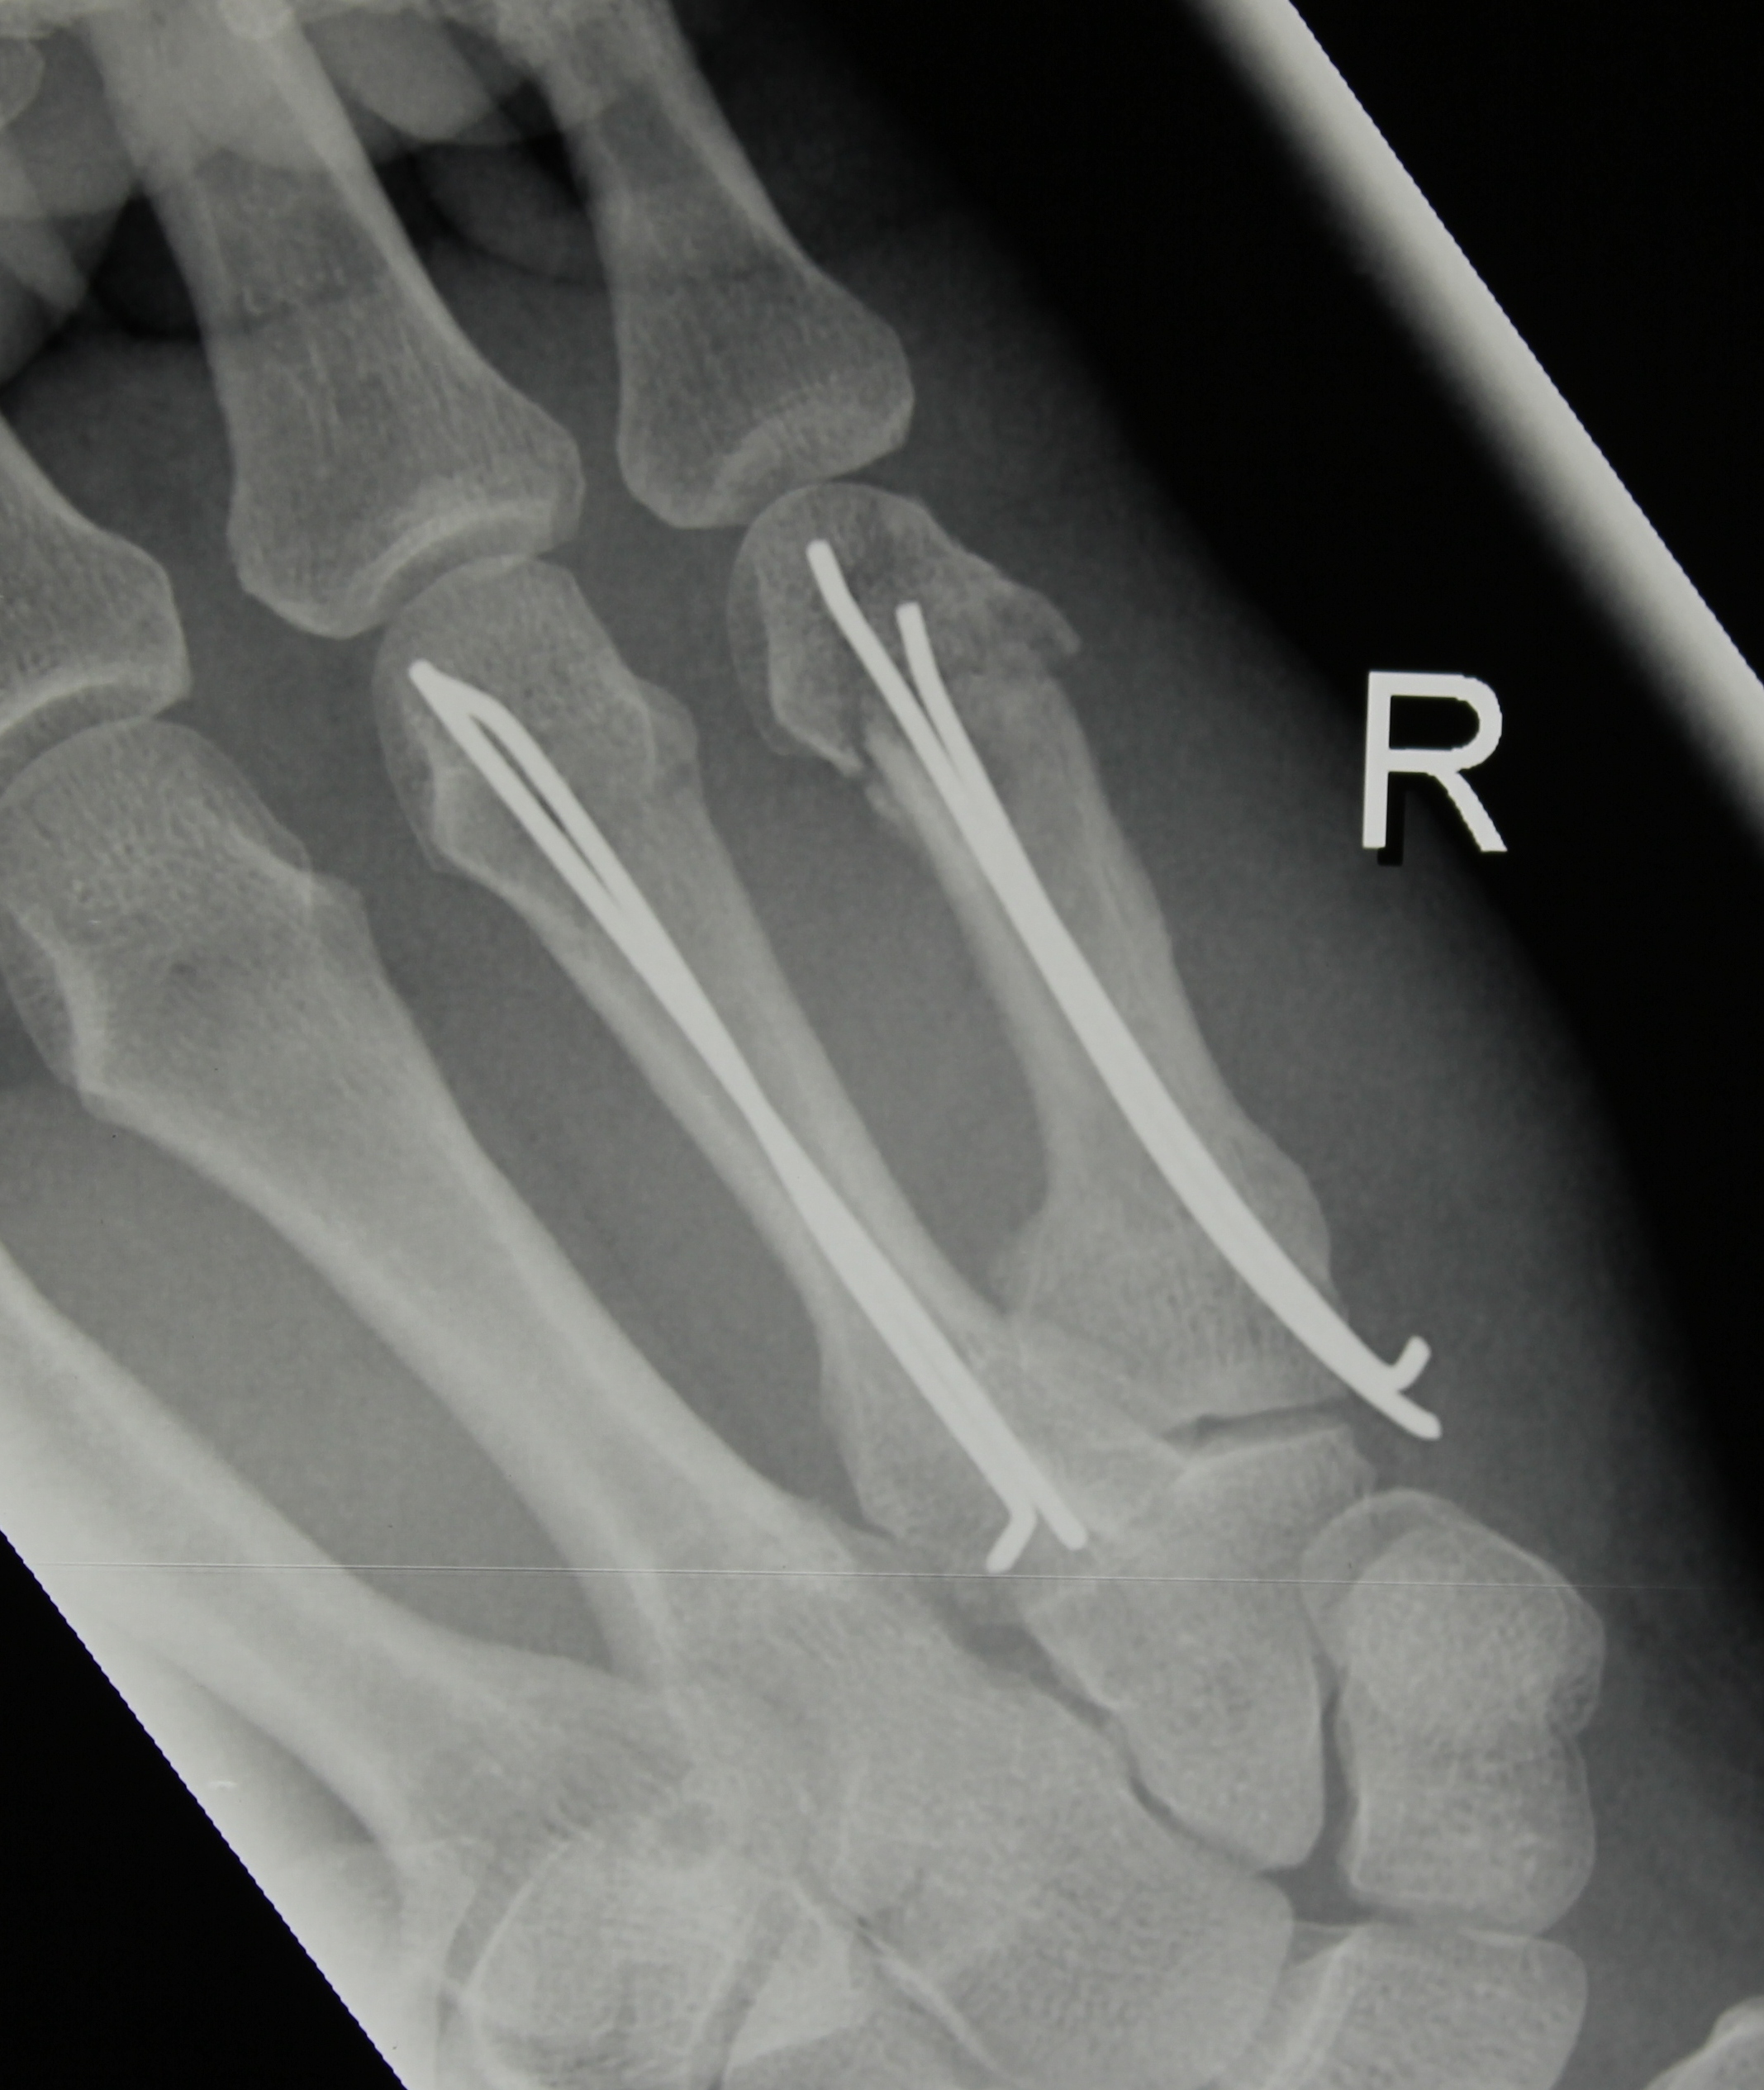

Hsu LP, Schwartz EG, Kalainov DM, Chen F, Makowiec RL. Complications of K-wire fixation in procedures involving the hand and wrist. J Hand Surg Am 2011;36(4):610-6.

Subramanian P, Kantharuban S, Shilston S, Pearce OJ. Complications of Kirschner-wire fixation in distal radius fractures. Tech Hand Up Extrem Surg 2012;16(3):120-3.

Abul A, Karam M, Al-Shammari S, Giannoudis P, Pandit H, Nisar S. Peri-operative antibiotic prophylaxis in K-wire fixation: a systematic review and meta-analysis. Indian J Orthop 2023;57(7):1000-7.

Ridley TJ, Freking W, Erickson LO, Ward CM. Incidence of treatment for infection of buried versus exposed Kirschner wires in phalangeal, metacarpal, and distal radial fractures. J Hand Surg Am 2017;42(7):525-31.

Lakshmanan P, Dixit V, Reed MR, Sher JL. Infection rate of percutaneous Kirschner wire fixation for distal radius fractures. J Orthop Surg (Hong Kong) 2010;8(1):85-6.